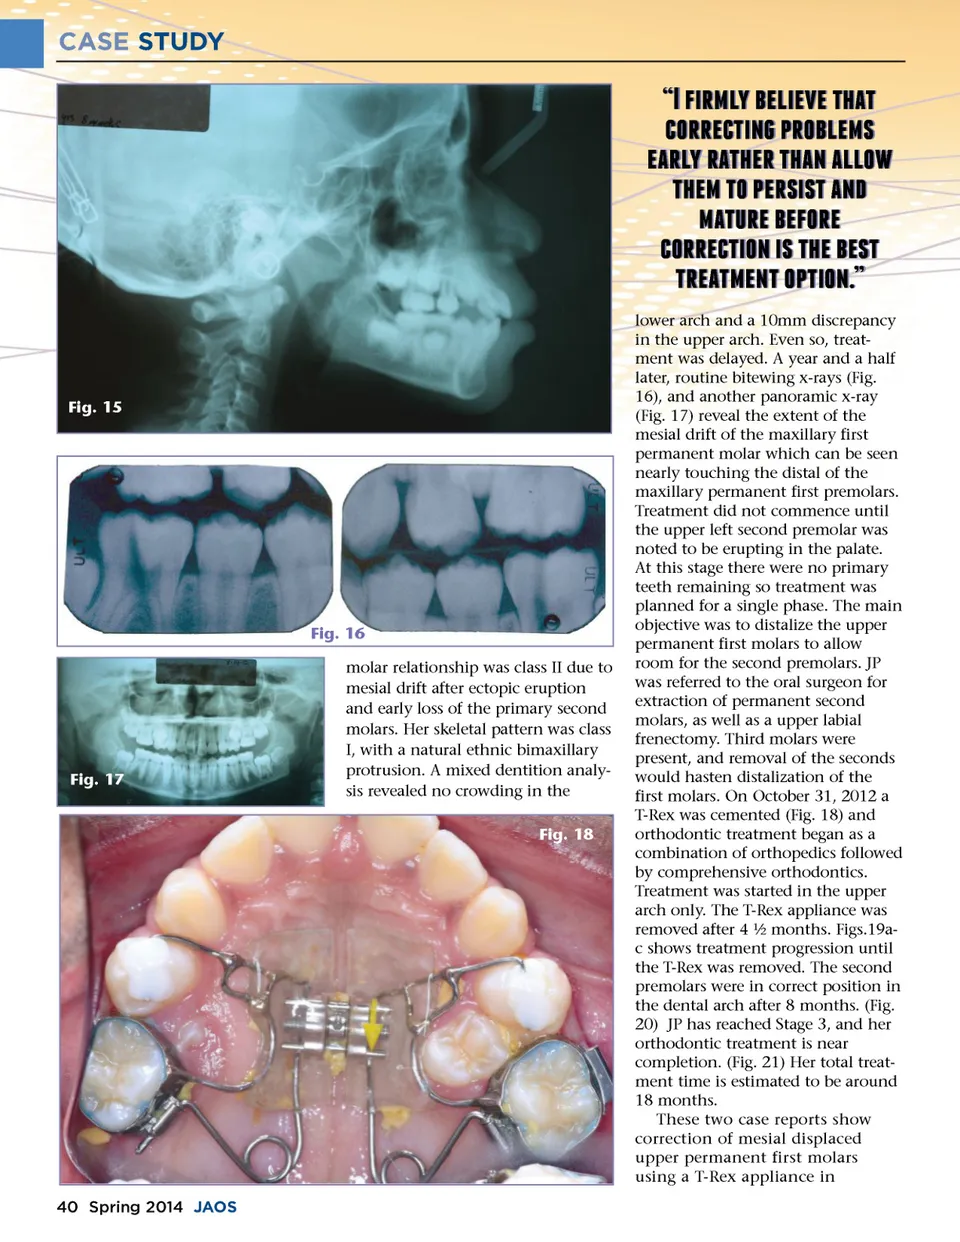

CASE STUDY �c;! b;e;! b;  !f;d;f; c;e;e; f;b;! e;c; a; d;e;!e;d;f; e;!f;d;!d;c; f; !f;c;! e;a;b;a;f;!d;�f; d;f;�e;e; ! c;e; c;e;e; f;b;c;!b;a;!f; ! a;f; f;e; d;f; f;!c; f;b;c;  lower arch and a 10mm discrepancy in the upper arch. Even so, treat-ment was delayed. A year and a half later, routine bitewing x-rays (Fig. 16), and another panoramic x-ray (Fig. 17) reveal the extent of the mesial drift of the maxillary first permanent molar which can be seen nearly touching the distal of the maxillary permanent first premolars. Treatment did not commence until the upper left second premolar was noted to be erupting in the palate. At this stage there were no primary teeth remaining so treatment was planned for a single phase. The main objective was to distalize the upper permanent first molars to allow room for the second premolars. JP was referred to the oral surgeon for extraction of permanent second molars, as well as a upper labial frenectomy. Third molars were present, and removal of the seconds would hasten distalization of the first molars. On October 31, 2012 a T-Rex was cemented (Fig. 18) and orthodontic treatment began as a combination of orthopedics followed by comprehensive orthodontics. Treatment was started in the upper arch only. The T-Rex appliance was removed after 4 ½ months. Figs.19a-c shows treatment progression until the T-Rex was removed. The second premolars were in correct position in the dental arch after 8 months. (Fig. 20) JP has reached Stage 3, and her orthodontic treatment is near completion. (Fig. 21) Her total treat-ment time is estimated to be around 18 months. These two case reports show correction of mesial displaced upper permanent first molars using a T-Rex appliance in Fig. 15 Fig. 16 molar relationship was class II due to mesial drift after ectopic eruption and early loss of the primary second molars. Her skeletal pattern was class I, with a natural ethnic bimaxillary protrusion. A mixed dentition analy-sis revealed no crowding in the Fig. 18 Fig. 17 40 Spring 2014 JAOS